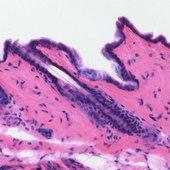

Mouse skin, stained with Haematoxylin (purple) and Eosin (pink).

Haematoxylin stain is commonly followed (or counterstained) with another histologic stain, eosin.[10][11][1] When paired, this staining procedure is known as H&E staining, and is one of the most commonly used combinations in histology.[1][12][7][14] Haematoxylin is also a component of the Papanicolaou stain (or PAP stain) which is widely used in the study of cytology specimens, notably in the PAP test used to detect cervical cancer.[14][1]

Principally used as a nuclear stain (to stain the cell nucleus), haematoxylin will also stain rough endoplasmic reticulum, ribosomes, collagen, myelin, elastic fibers, and acid mucins.[10] Haematoxylin alone is not an effective stain, but when oxidized to hematein, and combined with a mordant, stains chromatin in cell nuclei dark blue to black.[1][7][25][10] The colour and specificity of haematoxylin stains are controlled by the chemical nature, and amount, of the mordant used, and the pH of the staining solution, thus, a variety of haematoxylin formulations have been developed.[1][10][15]